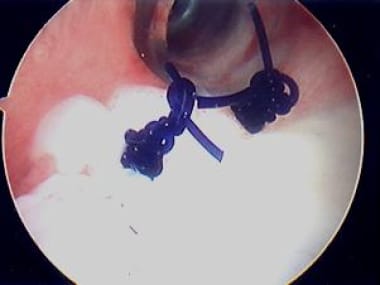

Sometimes, the labrum may be deficient, hypoplastic, abraded, or torn and thus insufficient for use via direct suture passage technique. In such a situation, suture anchors may be helpful (see the images below). The anchor is placed on the margin of the articular surface, and the attached suture is then passed through the capsule to achieve a standard "tuck," with or without the labrum if possible, to achieve a "caposulolabral reconstruction" and a "bumper-stop" configuration, to enhance stability.

Second of two anchors placed for posterior plication, given hypoplastic posterior labrum, prior to suture passage. Note anchor placement on posterior margin of articular surface, not on neck of glenoid. This allows for "capsulolabral reconstruction". See next image. Photo courtesy of Daniel C Wnorowski, MD.

After passage of anchor-based suture and completion of plication and "capsulolabral reconstruction," augmenting hypoplastic labrum with capsular fold. Note that these are permanent sutures and therefore are tied off glenoid to avoid knot-articular surface impingement. Photo courtesy of Daniel C Wnorowski, MD.